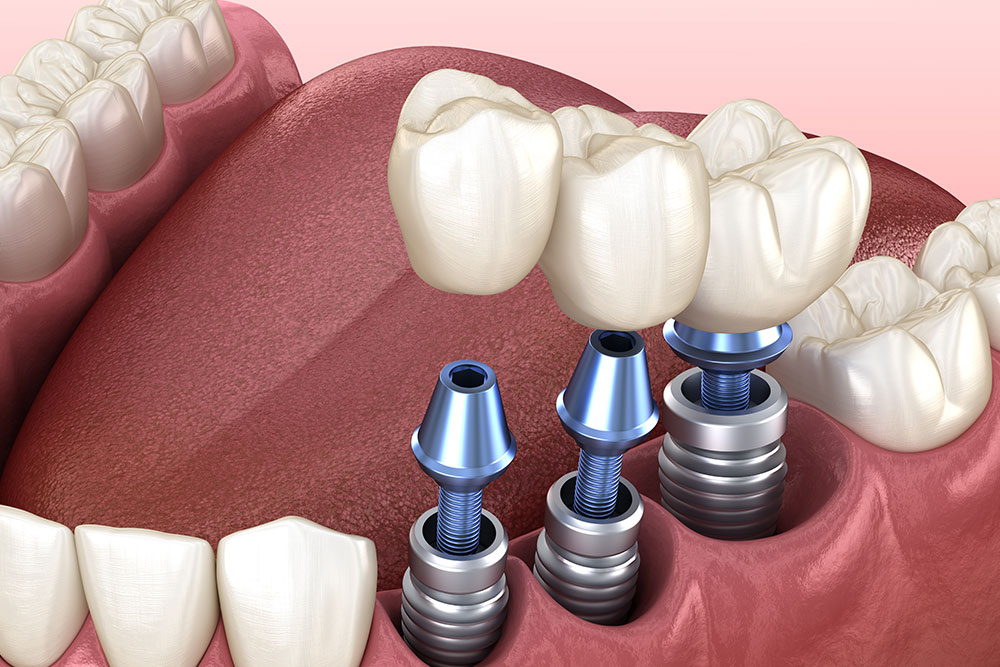

How To Adjust Emergence Profiles In Implant Procedures

The implant looked perfect on the X-ray. Its placement was spot on, and healing was …

5 Common Mistakes To Avoid When Placing Dental Implants

Dental implants offer patients permanent solutions for missing teeth, but correctly placing them takes skill, …

6 Dental Implant Tools Every Dentist Should Have

Dental implant procedures require precision, expertise, and the right set of tools. Using high-quality dental …